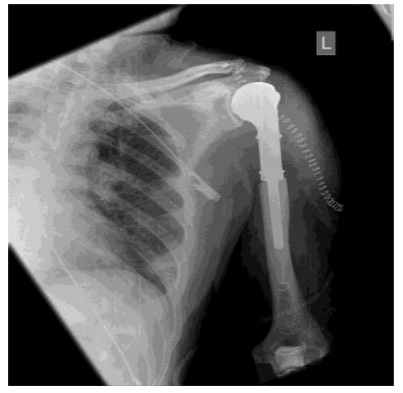

CASE 2: Kidney (renal cell) cancer metastasizes to the humerus bone.

Post-surgery: The procedure involves removing the tumorous portion of the bone and implanting a prosthesis.